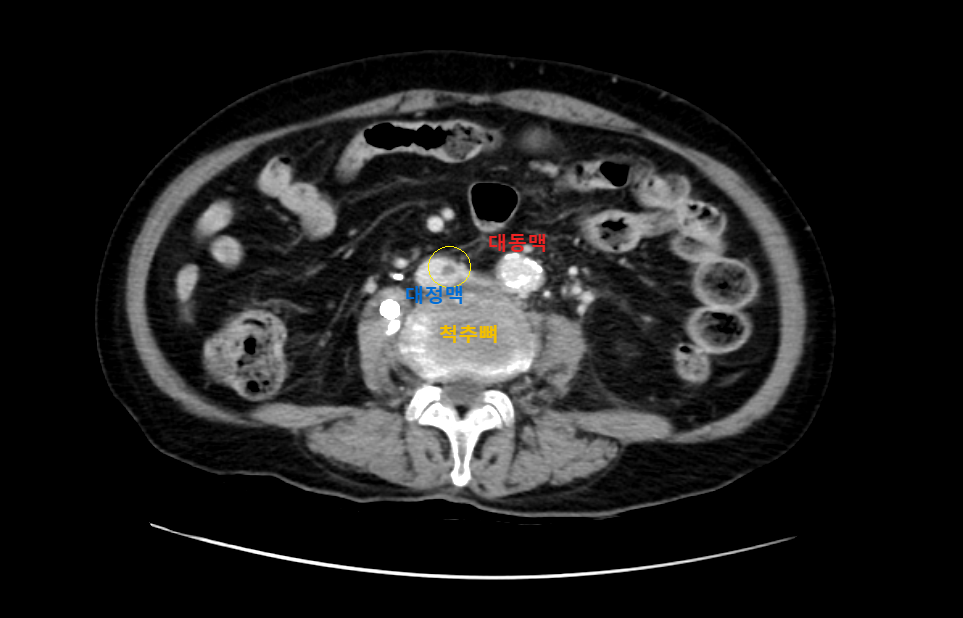

영상은 머리에 가까운 복부에서 다리 쪽으로 가는 순서로 나열하였다.

CT영상을 보면 좌측 장골정맥과 우측 장골동맥이 교차하는 지점에서부터 다리 말단 쪽으로 내려가며, 총장골정맥-외장골정맥-총대퇴정맥-표대대퇴정맥-오금정맥-경골정맥까지 혈전이 차있는 모습을 확인할 수 있었다.

Acute DVT, left CIV, EIV, IIV, CFV, SFV, popliteal and crural veins with compression of left CIV between vertebra and right CIA, c/w acute DVT with May Thurner syndrome.